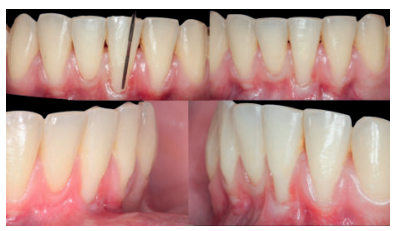

Se realizó control a la semana de la intervención (Figura 4) y tras 15 días se retiró la sutura, observando la revascularización del injerto y la epitelización del área cruenta apical al sobre (Figura 5). Se realizó seguimiento al mes (Figura 6), a los 3 meses (Figura 7) y al año y medio del procedimiento (Figura 8).

El control a la semana (Figura 13) presentaba inflamación moderada y a las 2 semanas (Figura 14) se retiraron los puntos de sutura. La paciente acudió a los 4 meses (Figura 15) y al año (Figura 16) a visitas de revisión, donde se apreció una buena banda de tejido queratinizado y una pequeña cicatriz.